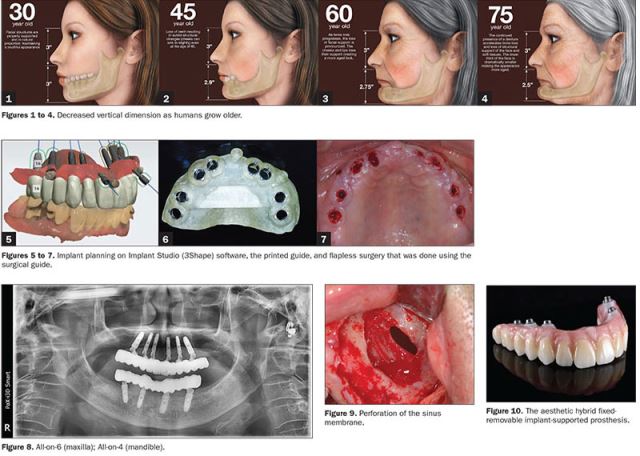

برای کاشت ایمپلنت فوری یا ایمپلنت یک روزه، نیازی نیست ابتدا مراحل چند ماهه جوش خوردن ایمپلنت به استخوان را پشت سر بگذارید و پس از آن روکش بر روی دندان تان نصب شود، بلکه در همان روزی که ایمپلنت در دهانتان قرار می گیرد روکش دندان هم بر روی آن نصب می شود. در درمان ایمپلنت به صورت دیجیتال به منظور بررسی استخوان فک و همچنین موقعیت قرار گرفتن رشته های عصبی، از مدل سازی کامپیوتر سه بعدی استفاده می شود. با این شرایط متخصص دندانپزشک با کمترین شکافی به کاشت ایمپلنت دندان می پردازد. به دلیل شکاف کمتر در این روش، درد کمتری برای بیمار وجود خواهد داشت. همچنین به دلیل قرار گرفتن اطلاعاتی بسیار دقیق در دست متخصص دندانپزشک، کمترین میزان آسیب و خطا در این نوع روش درمانی دیجیتال وجود دارد. در کاشت ایمپلنت دیجیتال برای جلوگیری از آسیب عصب و دندان های کناری، یک هدایت کننده (گاید جراحی) بر روی دندان ها نصب می شود. که همین راهنما به برش های دقیق و کوچک تر متخصص دندانپزشک کمک می کند.

در این مرحله به کمک اسکنر دهانی تصویری دیجیتالی تهیه شده که تمامی آناتومی دندان و بافت لثه را ثبت می کند.

برای ضبط دقیق تر آناتومی استخوان و دندان ها، در مرحله ی دوم یک سی تی اسکن پرتو مخروطی انجام می گیرد. در این سی تی اسکن، ساختاری سه بعدی از استخوان، سینوس ها و اعصاب به دست می آید. در ادامه تصاویر مرحله یک و دو با یکدیگر ترکیب شده و از دندان ها و استخوان دهان بیمار، مدلی سه بعدی ایجاد می شود.

در این مرحله پس از بررسی های لازمه قطر و طول ایمپلنت انتخاب می شود. پس از اینکه متخصص دندانپزشک طرح مورد نظر را تصویب کرد، مرحله بعدی انجام می گیرد.

در این مرحله به کمک CAD-CAM یک گاید به صورت قالب پلاستیکی ساخته می شود. این مرحله برای قرار دادن ایمپلنت نهایی بسیار کمک دهنده می باشد. گاید تهیه شده در دهان بیمار قرار داده می شود تا بدون برش ایمپلنت درون جایگاه مورد نظر قرار بگیرد.

در مرحله آخر و در روز جراحی و بلافاصله بعد از قرار دادن ایمپلنت، روکش ایمپلنت که دارای ظاهری بسیار طبیعی و زیبا می باشد، برای بیمار نصب خواهد شد. در واقع در روش ایمپلنت دیجیتال، بیمار حتی یک روز هم بدون دندان نمی ماند.